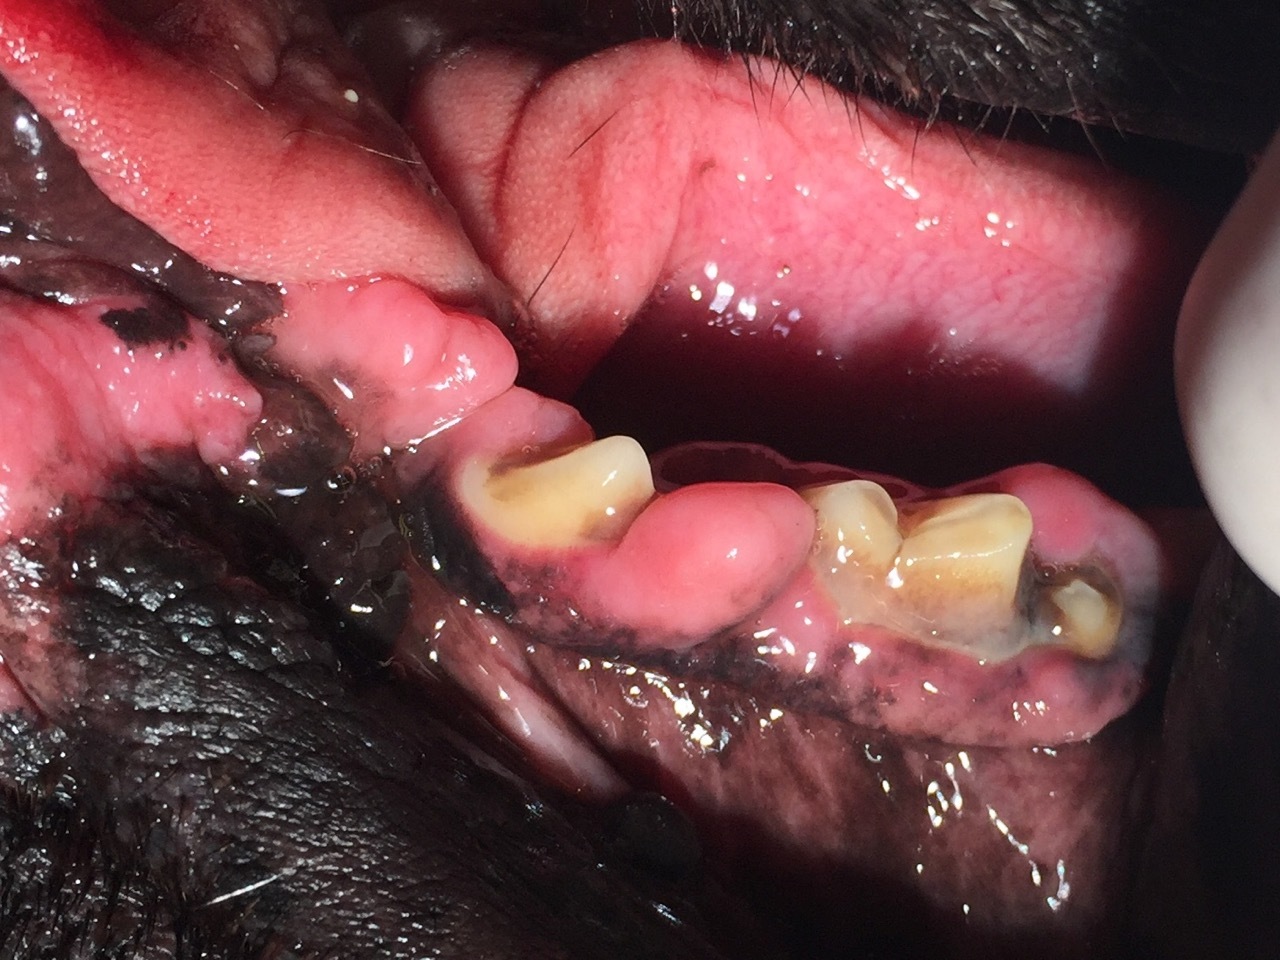

Dann sahen wir uns die Maulhöhle an, in der wir insgesamt 24 Lokalisationen am Zahnfleisch markieren konnten, die behandlungsbedürftig waren. (Abb. 1-4). Das Zahnfleisch wies sogenannte periphere odontogene Fibrome auf, die umgangssprachlich auch als Epuliden bezeichnet werden. Der Boxer, die Bordeaux Dogge, der Mops und die Französiche Bulldogge weisen hier eine Prädisposition auf, haben also eine Veranlagung zur Ausbildung dieser Tumore.

Von der Einteilung bezeichnet man die Epuliden als gutartige Zubildungen, die dem Zahnfleisch aufsitzen. Sie bilden keine Metastasen (Tochtergeschwülste) aus. Allerdings können sie erhebliche Ausmaße annehmen, wie man anhand der Abb.3 sehen kann. Die Epuliden können somit sowohl zu einer mechanischen Einschränkung beim Zermahlen des Futters als auch zu entzündlichen Veränderungen führen, dadurch erhebliche Schmerzen verursachen und sogar Zähne verdrängen. Zusätzlich konnte man in allen vier Quadranten bei Inspektor eine Gingivahyperplasie verzeichnen, die sich durch überwuchernde Zahnfleischbereiche darstellt. Teilweise werden ganze Zähne überwachsen vom Zahnfleisch, so dass hier massive Taschen entstehen, die Futterreste, Haare und anderes Fremdmaterial aufnehmen (Abb 1). Die daraus folgenden Entzündungen, die sich bis auf den tieferen Zahnhalteapparat auswirken, bedingen einen Rückgang des Knochens. Die Parodontitis ist in vollem Gange und lässt sich nur noch stoppen, aber nicht mehr heilen. Betroffene Zähne werden ab einem Furkationsbefall Grad 3 (die Wurzelaufteilung liegt gut sondierbar frei) extrahiert.

Um die Inhalationsanästhesie so flach wie möglich zu fahren, greifen wir, wie in der Humanmedizin, auf eine Leitungsanästhesie zurück, so wie Sie es von Ihrem eigenen Zahnarzt gewohnt sind. Um die Anästhesiezeit für Inspektor möglichst kurz zu gestalten, wurde die komplette Sanierung der Maulhöhle in zwei Sitzungen vorgenommen. In der ersten Sitzung wurde ein kompletter Parodontalstatus erhoben: Vermessung der Parodontaltaschentiefe, Bestimmung des Plaqueanheftungsgrades an den einzelnen Zähnen, Bestimmung des Entzündungsgrades und aller Veränderungen der Schleimhaut, der professionellen Reinigung der Zahnkronen und der Zahnhälse, dem Kürettieren (Auskratzen) der Zahnfleischtaschen und abschließender Zahnpolitur (Glättung aller Zahnbereiche). Schließlich wurden alle Zubildungen mit dem Diodenlaser blutungsfrei abgetragen, die veränderten Bereiche einer pathohistologischen Untersuchung zugeführt und in allen vier Kieferquadranten ein physiologischer Zahnfleischsaum mittels Laser modeliert und die von Zahnfleisch "begrabenen" Zähne wieder freigelegt. Der Vorteil der Lasermedizin liegt hier ganz klar in der sofortigen Blutstillung. Pathogene Mikroorganismen werden abgetötet, es kommt also zu einer noch stärkeren Keimreduktion im behandelten Bereich. Ebenso hat der Laser eine schmerzhemmende und entzündungshemmende Wirkung, so dass die Tiere schon am nächsten Tag wieder ohne Einschränkungen ihre Nahrung zerkleinern können. Von allen Zahnwurzeln wurden mit einem digitalen Dentalröntgengerät Bilder angefertigt und schließlich der Behandlungsplan für die zweite Sitzung erstellt, in der noch einige Zähne aufgrund einer fortgeschrittenen Parodontitis gezogen werden mussten.